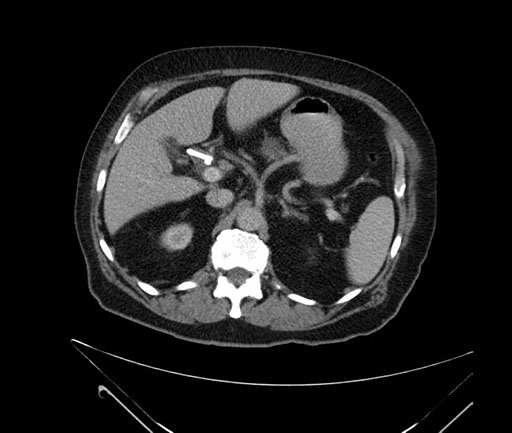

Imaging Analysis

Look through the patient's CT scan to identify any areas of concern for the necessary procedure.

Based on your CT findings, which issue(s) would give reason for "planned slowing down moment(s)" in this case?